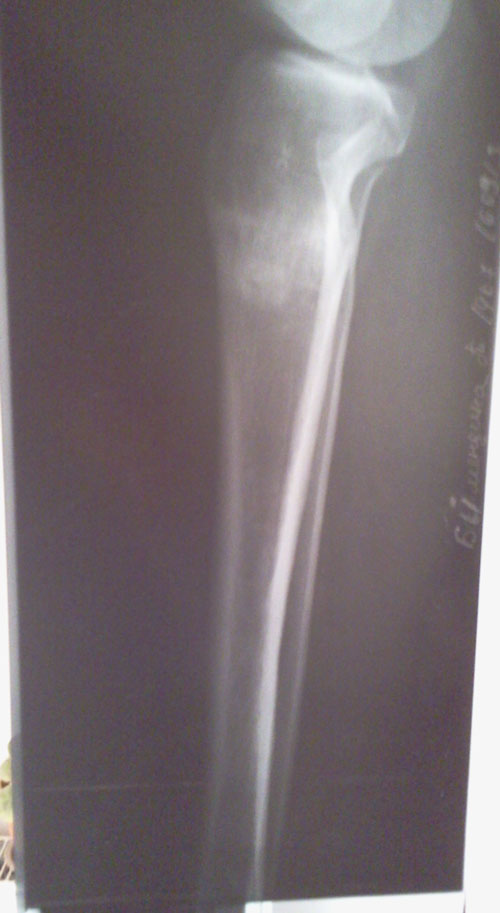

Рентген перед снятием аппаратов.

Сращение 100% - ое, отличная работа доктора!

Здравствуйте, Настя! Мы рады, что у вас всё хорошо! Боль в местах перелома пройдёт со временем (мало времени прошло). По результатам рентгена, все ограничения снимаются! Можете позволить себе всё! И ждём фото ножек!!!Здравствуйте, Николай Николаевич!

Извините за позднюю отправку контрольных снимков (от 18 сентября) после снятия аппаратов. Дата операции 10 апреля 2013г., дата снятия - 25-26 июля 2013г.

Самочувствие хорошее, нагрузку контролирую, каблук 3см, походка нормальная. Но иногда болят места переломов. Будут ли какие-либо рекомендации ?